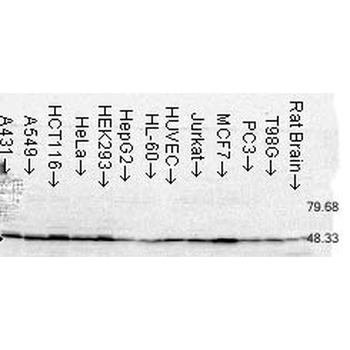

Anti-Cyclophilin A/PPIA Antibody [orb19174]

FC, ICC, IF, IHC, IHC-Fr, WB

Human, Mouse, Rat

Rabbit

Polyclonal

Unconjugated

10 μg, 100 μgCYPA Rabbit Polyclonal Antibody [orb100498]

FC, IF, IHC-Fr, IHC-P, WB

Bovine, Canine, Porcine, Rabbit

Human, Mouse, Rat

Rabbit

Polyclonal

Unconjugated